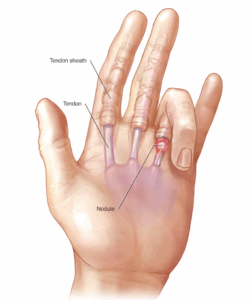

Trigger finger

Trigger finger makes a finger get stuck in a bent position. It may straighten suddenly with a snap. The fingers most often affected are the ring finger and the thumb, but the condition can affect any finger.